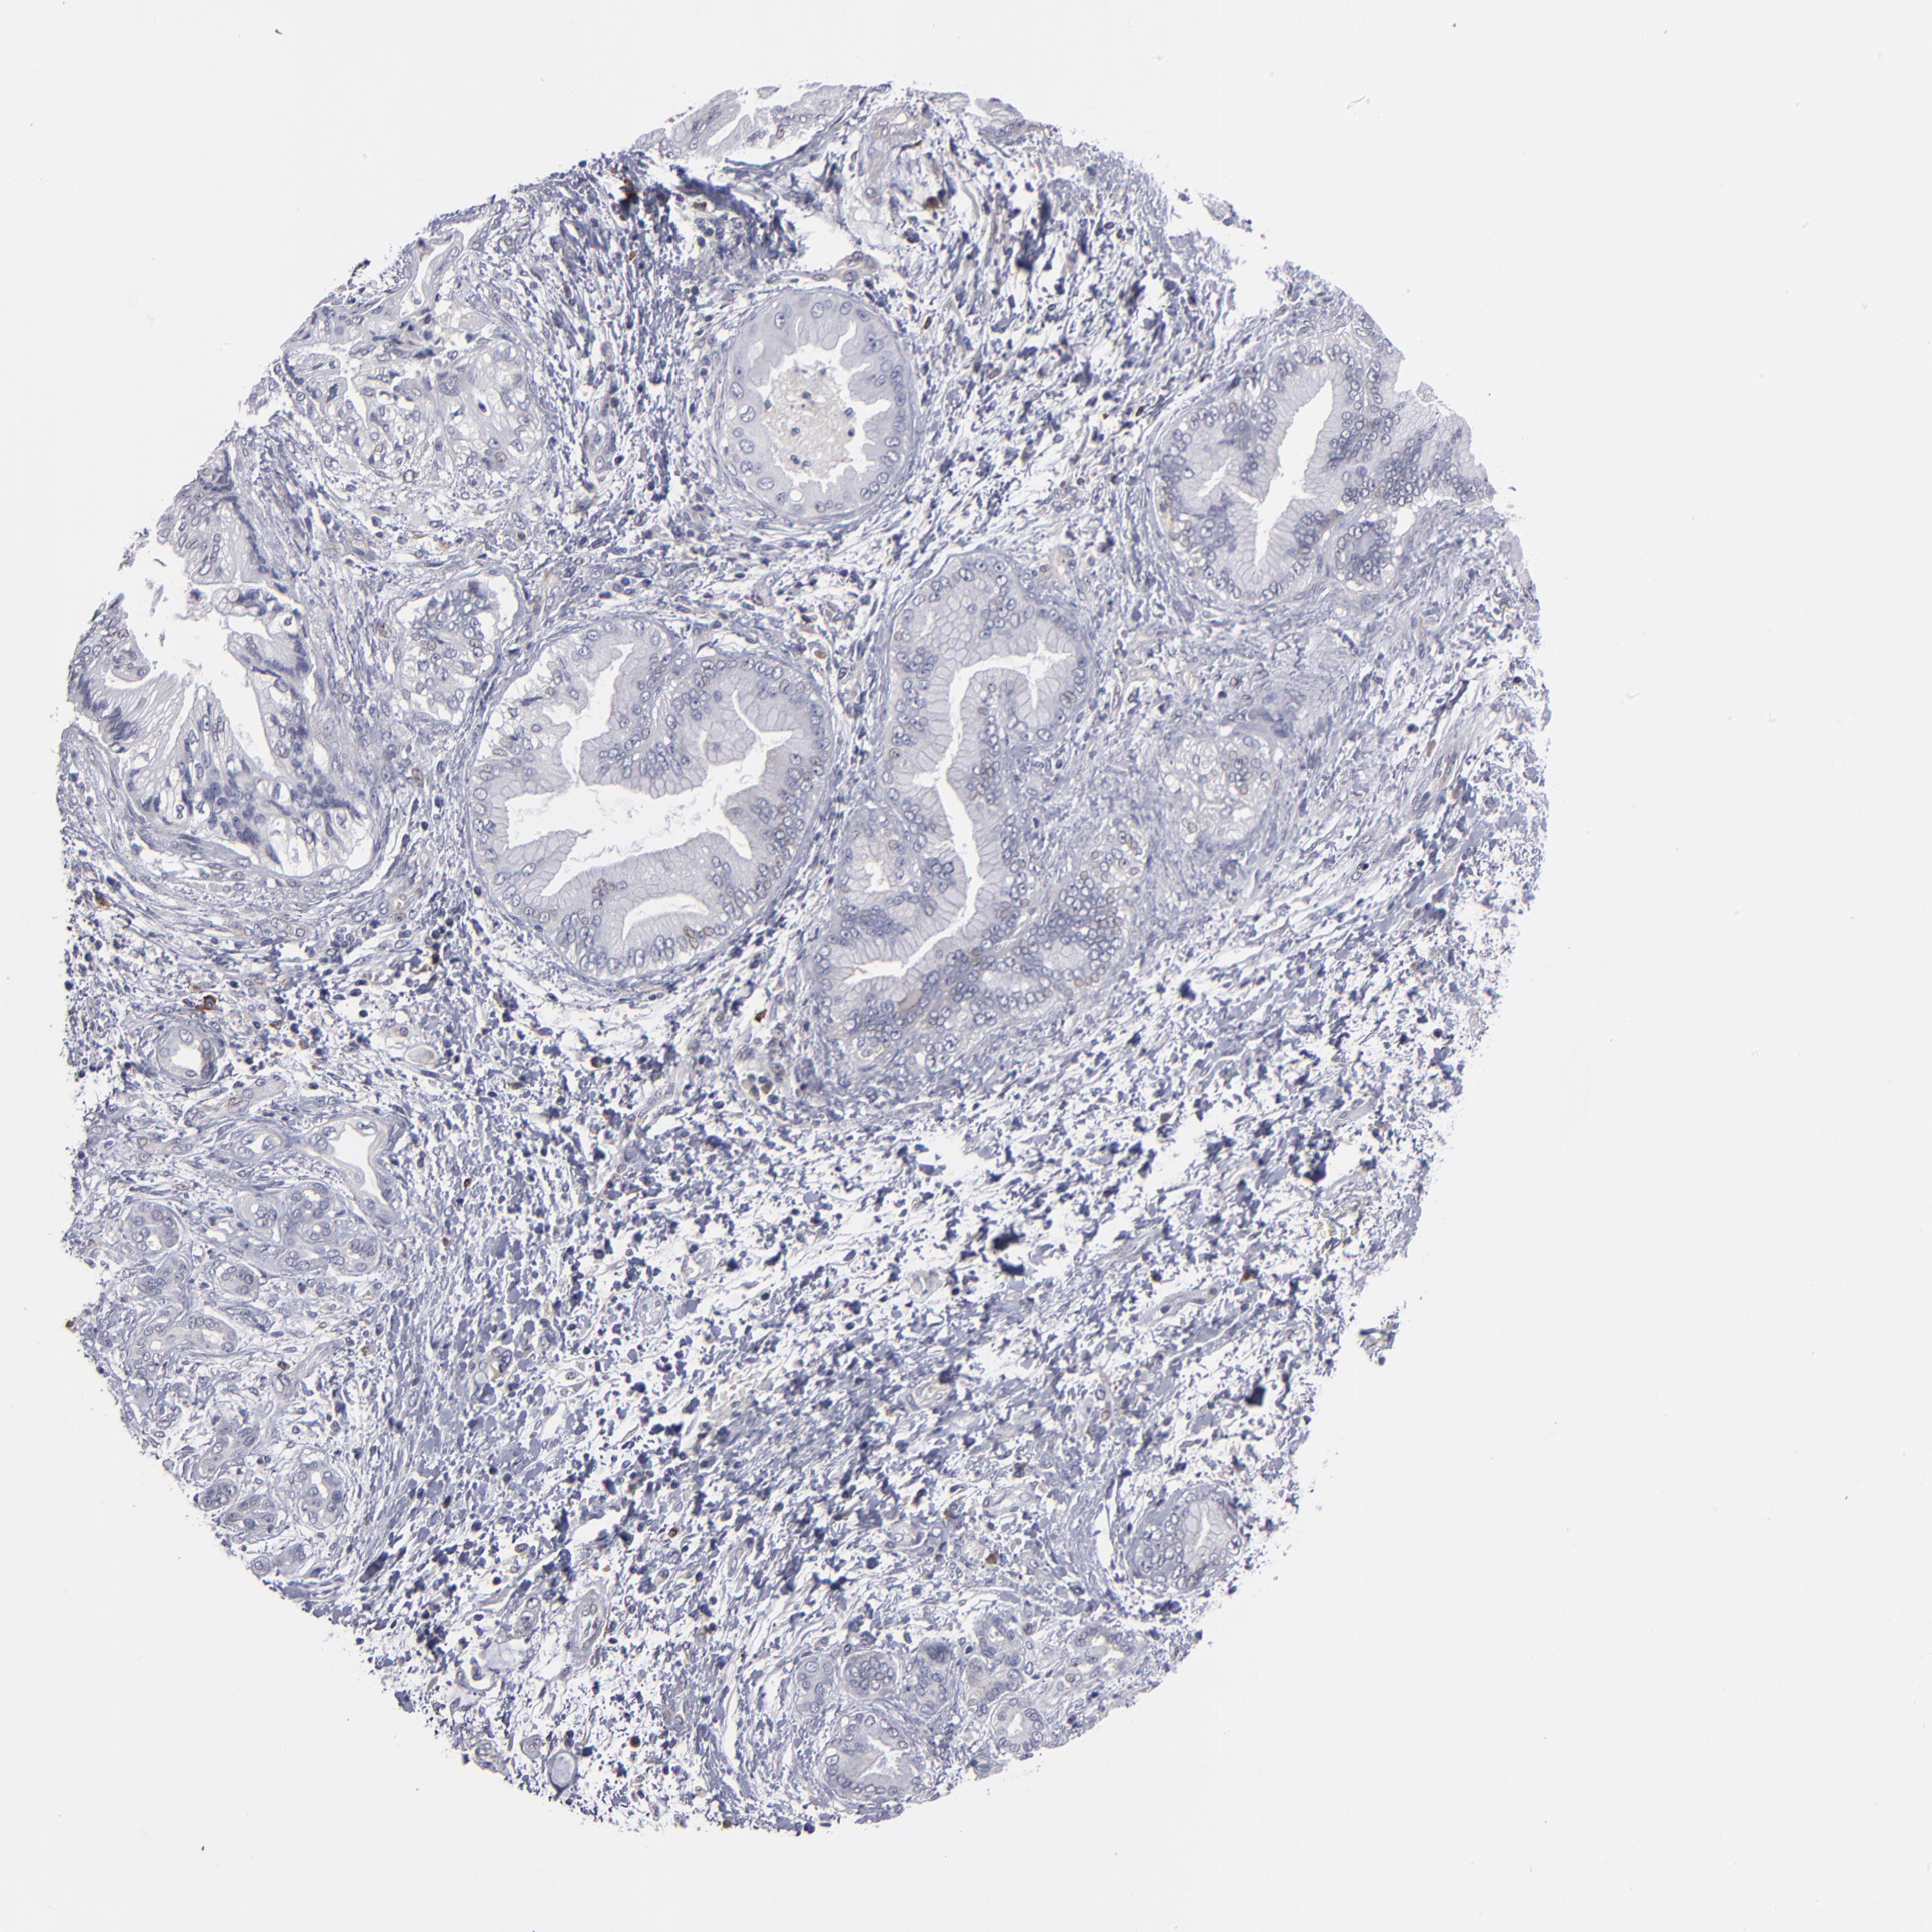

PANCREATIC CANCER - Protein expressioni

A mouse-over function shows sample information and annotation data. Click on an image to view it in a full screen mode. Samples can be filtered based on level of antibody staining by selecting one or several of the following categories: high, medium, low and not detected. The assay and annotation is described here.

Note that samples used for immunohistochemistry by the Human Protein Atlas do not correspond to samples in the TCGA dataset.

Antibody stainingi

Antibody staining in the annotated cell types in the current human tissue is reported as not detected, low, medium, or high, based on conventional immunohistochemistry profiling in selected tissues. This score is based on the combination of the staining intensity and fraction of stained cells.

Each image is clickable and will lead to virtual microscopy that enables deeper exploration of all samples and also displays staining intensity scores, fraction scores and subcellular localization as well as patient and tissue information for each sample.

Antibody HPA002980

Staining

High

Medium

Low

Not detected

Intensity

Strong

Moderate

Weak

Negative

Quantity

>75%

75%-25%

<25%

None

Location

Nuclear

Cytoplasmic/membranous

Cytoplasmic/membranous,nuclear

Adenocarcinoma, NOS